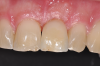

The survival rates of ceramic dental implants have already approached those of titanium implants in the evidence-based indications of "single-tooth restoration" and "three-unit bridge."7 They are on a par with most titanium systems today.8 Although long-term data has yet to confirm these good results, the success so far is encouraging such that clinicians are taking advantage of the clinical benefits of zirconium dioxide in daily practice and using ceramic implants as an additional option in the treatment spectrum alongside titanium implants (Figure 1). Indeed, even titanium, as highly regarded as it is, does not seem to be entirely free of problems.

Fig 1. Titanium (left) and zirconia (right) implants.

Figure 1